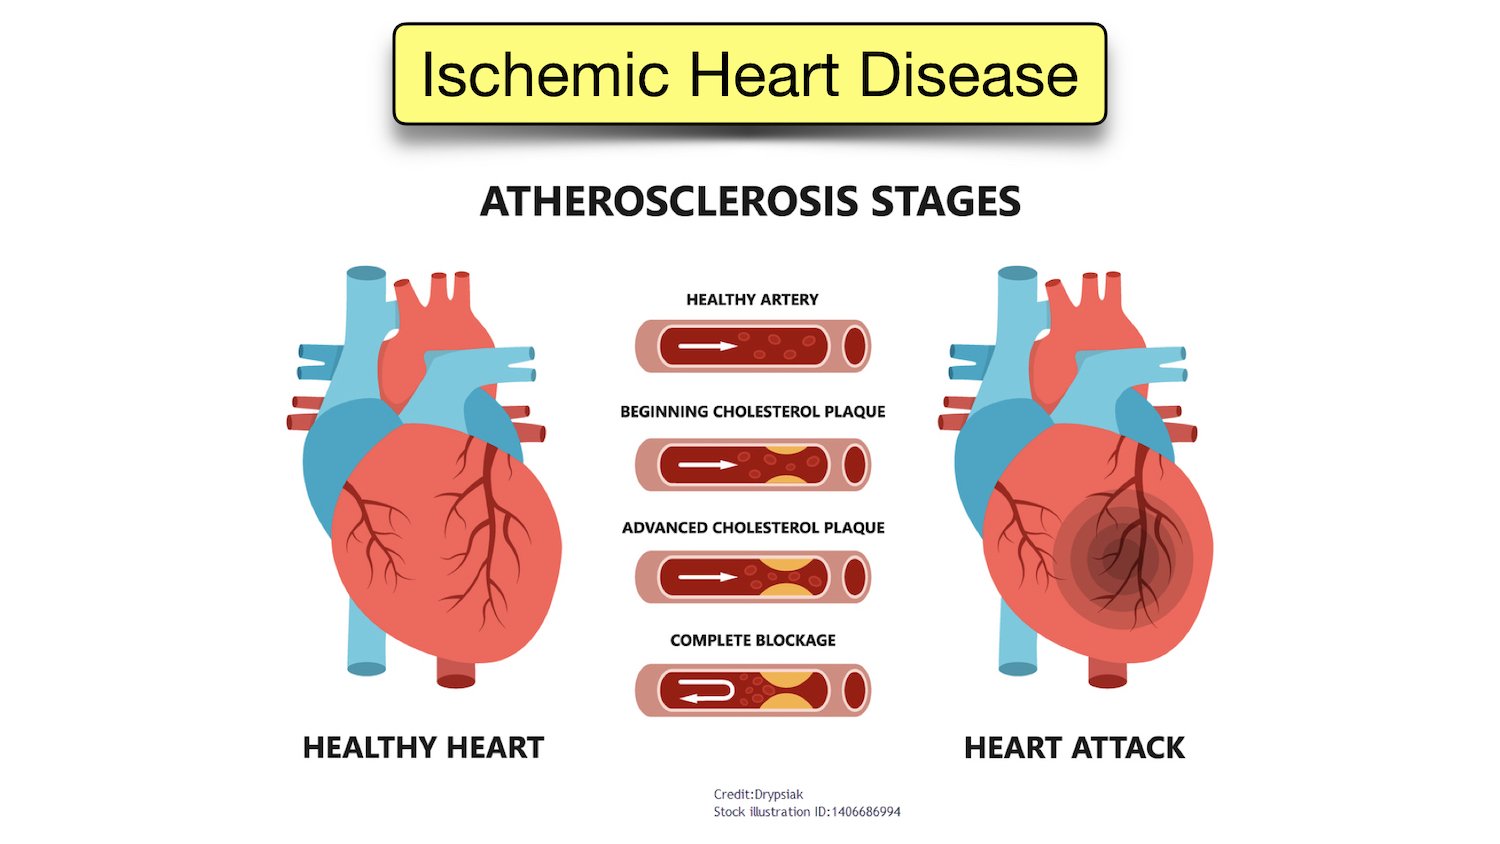

ICD-10-CM Medical Code Lookup: Ischemic Heart Disease, Heart,

ICD-10-CM Medical Code Lookup: Ischemic Heart Disease, Heart, Heart disease could hit up to 28 years sooner for people,